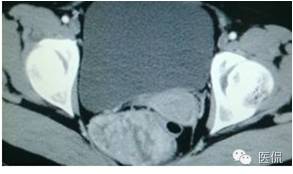

手术是:盆腔占位,病理为:血管肌纤维母细胞瘤。与肛门粘连,于是同时做了肛门的处理。